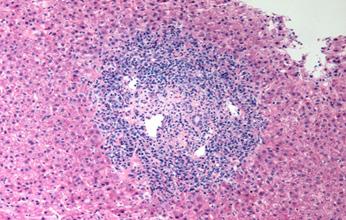

Figura 77. Colon en la enfermedad de Crohn. Imagen endoscópica que muestra ulceraciones lineales y serpiginosas Figura 78. Enfermedad de Crohn → Formación de granulomas sin necrosis caseosa (ENAM 2016) Tabla 06. Marcadores de actividad en la colitis ulcerosa

♦ Formación de pseudopólipos y abscesos crípticos (acúmulo de PMN en la luz de las criptas) (ENAM EXTRA 2021)